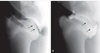

Figure 98-5. (A) An arthroscopic image demonstrating elevation of an OCD lesion of the humeral head (H). (B) A probe is inserted into a cystic defect in the glenoid cavity (G). (C) Use of a motorized burr to débride a lesion in the glenoid cavity.

C) Use of a motorized burr to débride a lesion in the glenoid cavity.Figure 98-5. (A) An arthroscopic image demonstrating elevation of an OCD lesion of the humeral head (H). (B) A probe is inserted into a cystic defect in the glenoid cavity (G). (C) Use of a motorized burr to débride a lesion in the glenoid cavity.